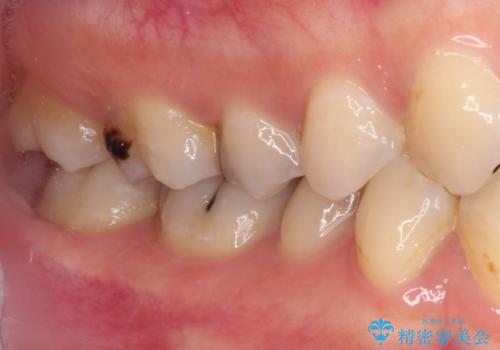

放置した虫歯 根管治療とオールセラミッククラウン

- 奥歯の虫歯を放置してしまい、痛みを感じることがあるとのことで来院された患者様です。

術前の診査では、神経を取り除かなくても済む可能性が示唆されましたが、実際に虫歯除去を進めたところ、レントゲン写真から読み取れる通り、神経組織にまで虫歯が及んでいることが分かりました。

速やかにラバーダム下にて根管治療を行うこととし、その後オールセラミッククラウンにて補綴治療を行うこととしました。

治療期間中、痛みが生じることはなく、処置後3か月経過しましたが良好な状態を保っています。